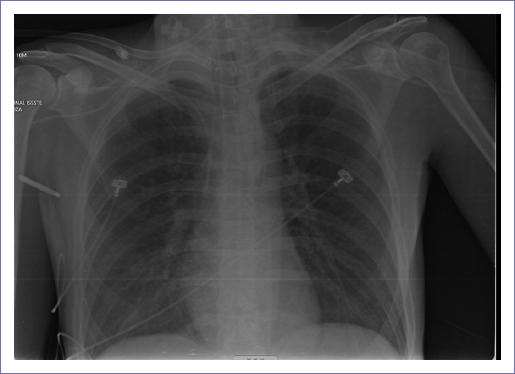

Tras resolver la inestabilidad hemodinámica, la radiografía de tórax (Fig. 6) no evidencia zonas de consolidación, por lo que se considera que las zonas de consolidación pulmonar reportadas en la tomografía de tórax se debieron a una descarga de catecolaminas y sobrecarga de volumen a nivel pulmonar. Los resultados de laboratorio muestran un descenso de la hemoglobina de 9.5 g/dl (previa de 15.8 g/dl, 2 días antes), que puede ser explicado por hemodilución, ya que tras la redistribución de líquidos se reporta normal. También presentó hiperglucemia de 250 mg/dl, así como lesión renal aguda (urea de 91 y creatinina de 2.1) y transaminasemia (aspartato aminotransferasa 537, alanina aminotransferasa 2,163 y deshidrogenasa láctica 658); esta última puede explicarse por hígado de choque.